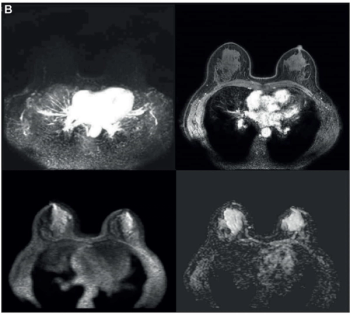

A partial response rate to neoadjuvant chemotherapy on mid-treatment MRI preceded a higher pathologic complete response (pCR) in 61.5 percent of women with triple-negative breast cancer, according to research presented at the American Society of Clinical Oncology (ASCO) conference.